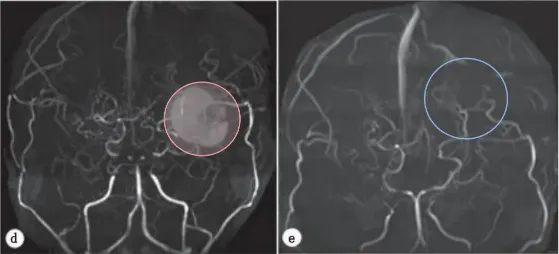

术后一个月,在对侧进行了同样的手术。两次手术均未导致高灌注综合征。双侧手术后,桃子每6个月进行一次MRI复查。

半年后,经随访DSA证实,侧支血循环明显改善,基底神经节中的烟雾血管减少。在脑XeCT检查中,两侧的脑血流量(CBF)也充分增加和改善(图2)。

图2:脑CTA显示首次搭桥术后显示良好的血管网络和基底烟雾血管消失,双侧脑血流得到改进。